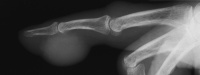

| This picture was sent

to the office from a nursing home clinic. The patient had developed

this minimally tender mass over the previous week. |

| One day later, the

precipitation progressed and ruptured into a subepithelial collection. |